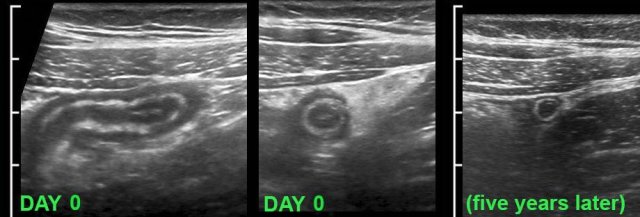

This young lady had typical signs of appendicitis for 24 hours (WBC 12 ,CRP 2).

US showed an inflamed appendix.

Within a period of hours her symptoms rapidly decreased and she was not operated.

US was performed 5 years later for other reasons and demonstrated a normal appendix.

In this patient, the appendix (arrow) on admission showed a dilated lumen and minimal surrounding fat. After the US examination the patient had rapidly subsiding symptoms and was not operated. Three days later he was symptom free and US showed a compressible appendix (arrow) with a slightly thickened wall and a collapsed lumen and surrounded by some inflamed fat. These images, the rather sudden resolution of symptoms and the usually low CRP, suggest that the cause of this phenomenon is relief of luminal obstruction at an early stage.